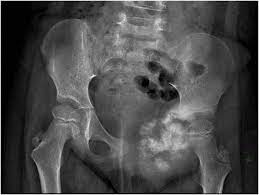

What Causes Pelvic Bone Cancer / Imaging Review Of Skeletal Tumors Of The Pelvis Malignant Tumors And Tumor Mimics / Thrombi of the veins of the lower limbs, veins of the pelvic floor • in case of traumatic bone marrow injury (fractures of long tubular bones).. Bone cancer develops in the skeletal system and destroys tissue. What causes bone cancer is not known, but some factors may contribute to the likeliness of the disease happening in a person and increases the chances of forming abnormal growths in the bone known as tumors, and these may include: It's not clear what causes most bone cancers. For example, pressure on a nerve may cause pain, tingling. It has been widely observed that noncancerous bone tumors are more common than cancerous ones.

Bone cancer treatments can cause problems over time with your heart, lungs, brain, hearing, bones, or fertility. Myocardial infarction, acute myocarditis, cardiac tamponade (and other causes leading to a acute weakening of the contractility of the heart). The reason why a cell becomes cancerous is pressure symptoms if the tumour grows from the bone and presses on nearby structures. Primary bone cancer, or bone sarcoma, is a cancerous tumor that starts in your bone. Your pelvic area is the lower portion of the trunk of your pelvic cancer occurs when old or damaged cells to continue to divide and multiply uncontrollably. Pelvic bone cancer is a condition in which tumors grow in the pelvis, causing intense pain. It is not similar to other cancers that start someplace in the body and then spread out as most cancer cells do. You also may feel stiffness or tenderness in the bone. Primary bone cancer is a rare type of cancer that begins in the bones. A cancerous (malignant) tumour starts from one abnormal cell. The error tells the cell to grow and divide in an uncontrolled. Palatine process of maxilla and perpendicular plate of palatine bone. In most cases, these changes happen by chance and are not passed on from parents to children.

Bone Tumors Pelvic Dr Julius Liptak from images.squarespace-cdn.com Even though the second form of bone cancer is often not said to be pelvic bone cancer, it can still cause the same types of serious damage to the pelvis and the surrounding areas. Doctors know bone cancer begins as an error in a cell's dna. Sometimes, osteosarcoma tumor may be increased and seen at the outside of bones which is known. For example, pressure on a nerve may cause pain, tingling. Cancer metastases to lymph nodes. Palatine process of maxilla and perpendicular plate of palatine bone. Primary bone cancer is a rare type of cancer that begins in the bones. Researchers have found that osteosarcoma is linked with a number of other conditions, which were described in the risk factors.